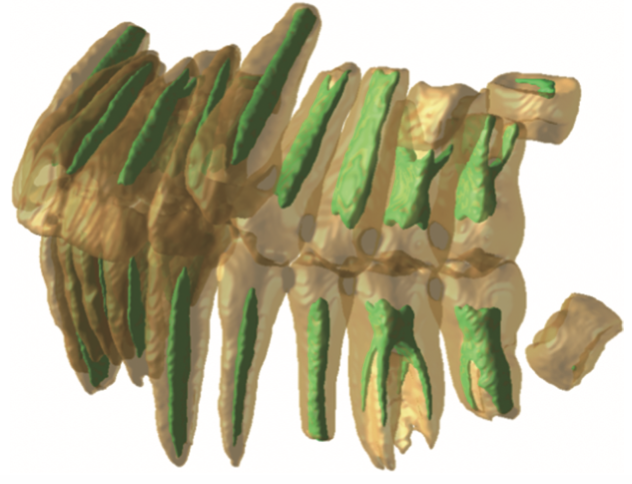

图:作者研究领域案例

第2部分深度剖析案例,涉及口腔医学、临床医学、材料学、工学等多个学科的交叉内容,是本书的重头戏。

通过 6 个真实的医学案例,展现人工智能技术在医学图像领域的应用,从医工交叉的角度出发,深入探讨了医学图像问题处理方法,旨在让读者了解如何将人工智能技术切实落地于医学图像学中,帮助相关从业者减少重复性工作,为医生和开发者两端搭建一座沟通的桥梁,进一步推广新技术和方法在该领域的应用。

图:书中介绍界面和展示编程效果的内容

另外,书中的六个案例均源自临床,囊括了口腔、心血管、肺部、肾脏等不同科室,作者对此进行了详细的剖析,每个案例都套用书中的流程模板展开,包括图像导入、图像标注、训练模型、数据增强、图像匹配等流程,在实例中巩固对流程的掌握,在运用流程中增加对实例的理解,既有实践参考意义,也更有助于读者快速上手。